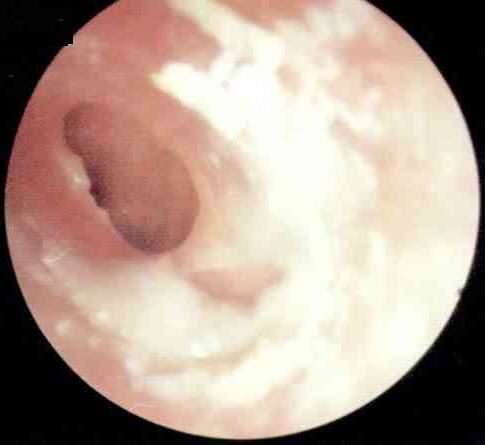

慢性化脓性中耳炎的症状诊断

慢性化脓性中耳炎是中耳粘膜、骨膜或深达骨质的慢性化脓性炎症,常与慢性乳突炎合并存在,拖延不治或治疗不当,可引起严重的颅内、外并发症而危及生命。慢性化脓性临床上以耳内反复流脓、鼓膜...[详细]